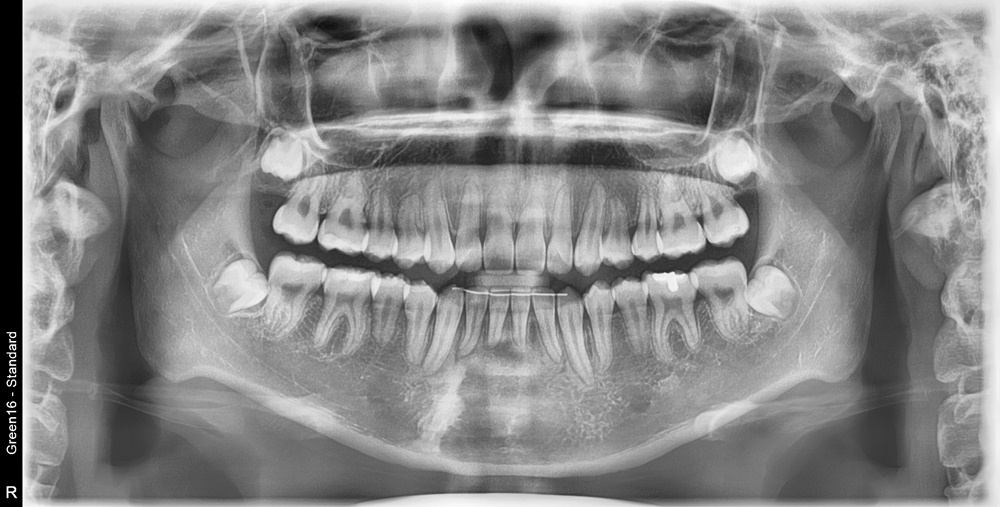

치료 후 사진입니다.